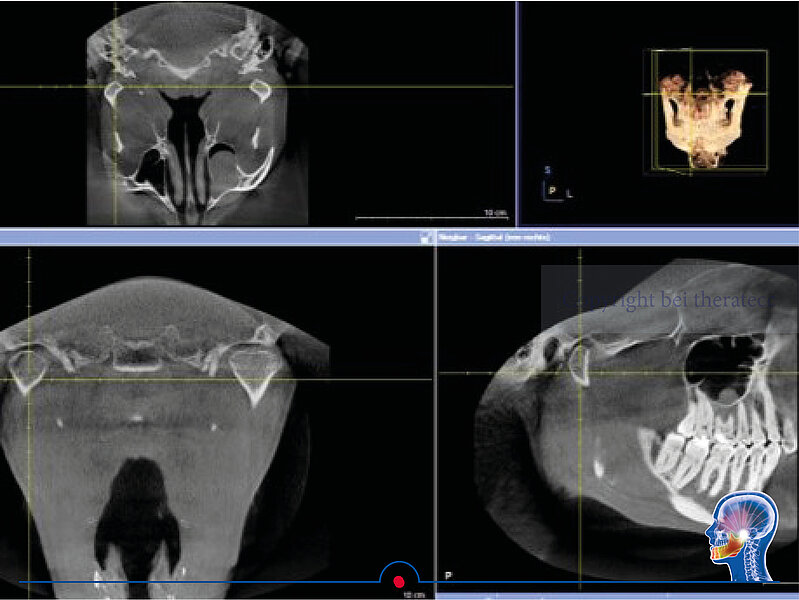

In diesem kurzen Video können Sie sehen, wie die Uk Bewegungen in Echtzeit in der Centric Software dargestellt werden. Der zentrische Bereich wird grün dargestellt.

In der Centric Software werden die Unterkieferbewegungen in Echtzeit visualisiert. Bei einer starken Belastung der Sensoren ist der Sensorwert hoch, bei einer geringen Belastung ist der Sensorwert entsprechend gering.

Dank des Stützstifts ist die Okklusion entkoppelt, unsere Patienten können den Unterkiefer also frei bewegen. Durch die beiden vertikalen Sensoren kann der höchste Bereich der beiden Fossae eindeutig dargestellt werden. Die anderen beiden Sensoren erfassen alle horizontalen Bewegungen. Damit wird in der Centric Software neben dem klassischen Pfeilwinkel auch der zentrische Bereich für den Anwender eindeutig visualisiert.

Damit sehen die Anwender genau, wann sich der Unterkiefer in zentrischer Relation befindet. Diese zentrische Relation kann sofort in eine analoge oder digitale Bissnahme überführt werden. Mit einem Luftkissen kann der 3D Sensor in dieser zentrischen Position im Mund des Patienten geblockt werden. Damit verbleibt ihr Patient in der gewünschten zentrischen Position. Die zentrische Bissnahme kann nun analog mittels Bisssilikon oder digital mittels eines Mundscanners durchgeführt werden.